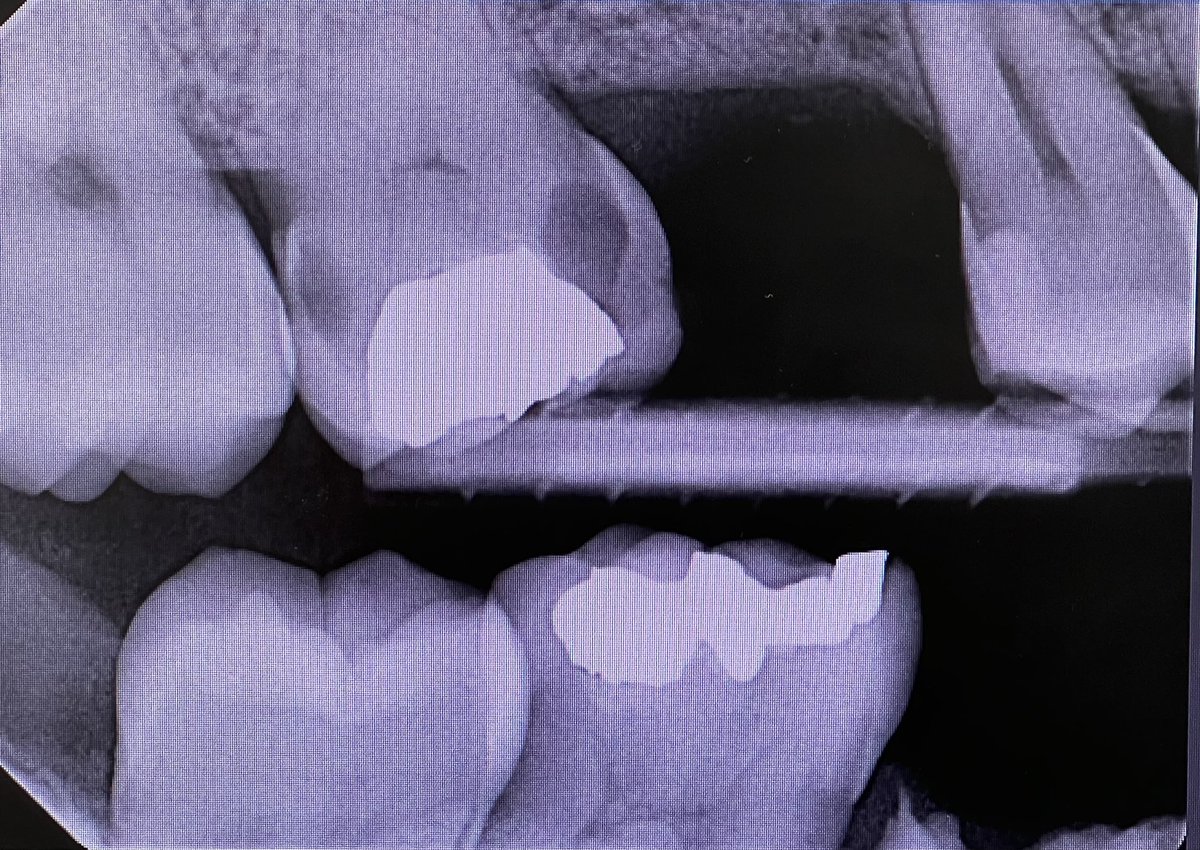

22 year-old male patient came to the clinic complaining of a broken tooth,

Class IV composite restoration was done on #11